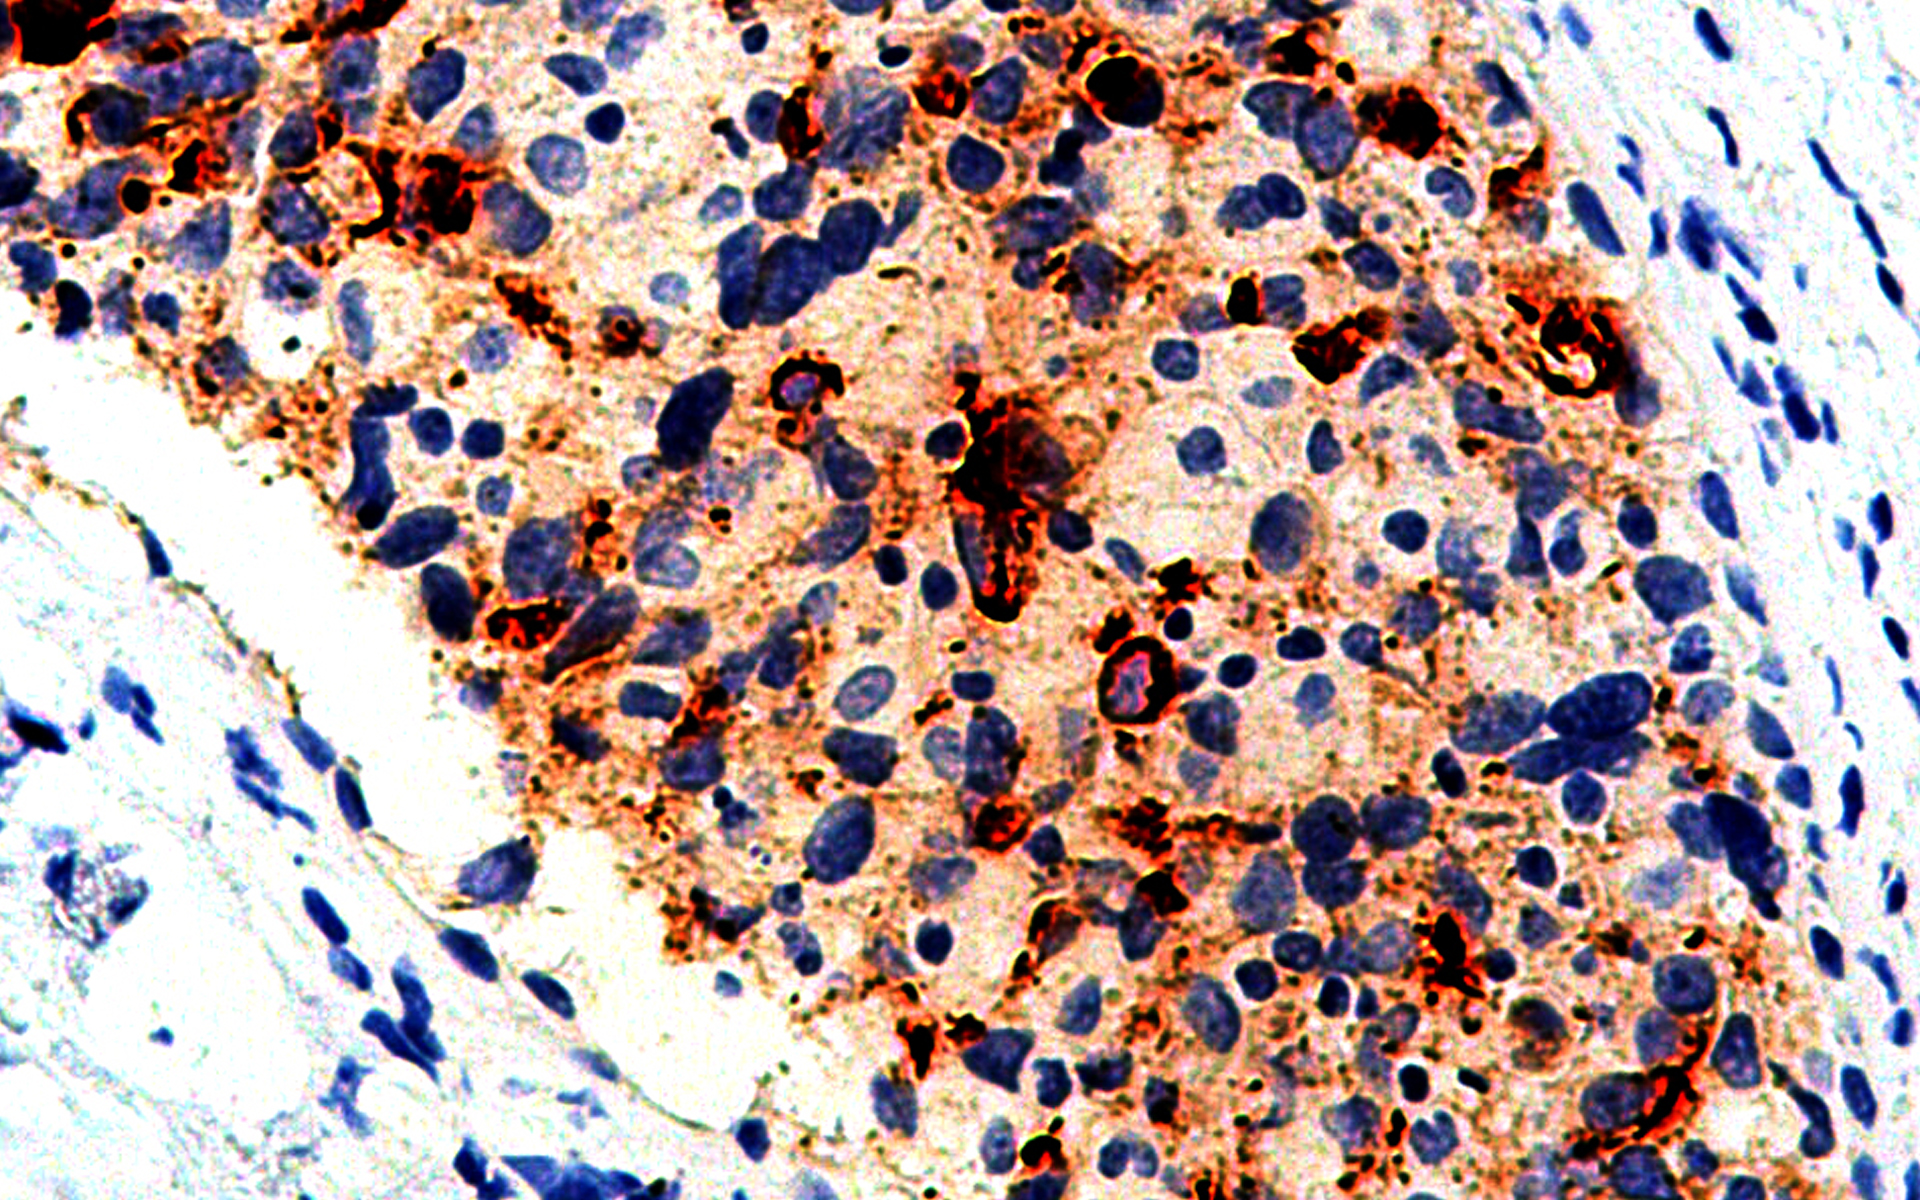

POSITIVE CONTROL:

Breast Carcinoma

The BCA-225 [IHC225] antibody is intended for qualified laboratories to qualitatively identify by light microscopy, the presence of associated antigens in formalin-fixed, paraffin-embedded (FFPE) tissue sections using immunohistochemistry test methods. Use of this antibody is indicated, subsequent to clinical differential diagnoses of diseases, as an aid in the identification of neoplastic tissues within the context of antibody panels, the patient’s clinical history and other diagnostic tests as evaluated by a qualified pathologist.